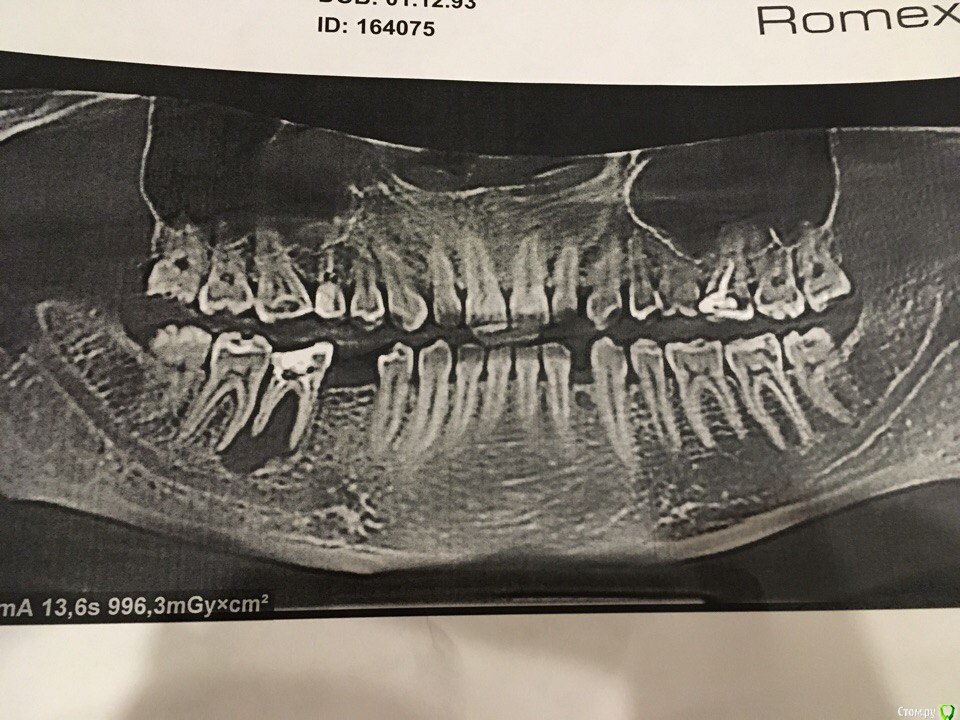

Дарья Лазаревна Опубликовано 15 ноября, 2017 Поделиться Опубликовано 15 ноября, 2017 Сегодня сделала КТ, слева на фото и с правой стороны зубов под 5 (или это 6- могу ошибиться) у меня дыра. Хирург одной из клиник сказал необходимо выдирать, заполнять костным материалом, а после лечения можно имплант вставить. Скажите какой еще есть выход из ситуации? кто то еще сталкивался с таким?В зубу много лет назад были вычищены канала, через какое то время он меня волновал-стонал, пломбу переделали в поликлинике по прописке и все, а сейчас вот такая история обнаружилась. Так же стоматологи говорят дальнейшее разрушение костного материала усугубит ситуацию.Расскажите кто что знает и какой информацией владеет в этой теме. Ссылка на комментарий

dok1 Опубликовано 11 декабря, 2017 Поделиться Опубликовано 11 декабря, 2017 И томограмму бы в идеале увидеть. Несколько срезов этого зуба. Ссылка на комментарий